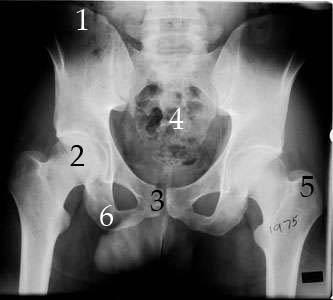

X-Rays

1. Iliac Crest

2. Head of Femur/Acetabulum

3. Pubic Symphysis

4. Sacrum

5. Greater Trochanter

6. Ischium